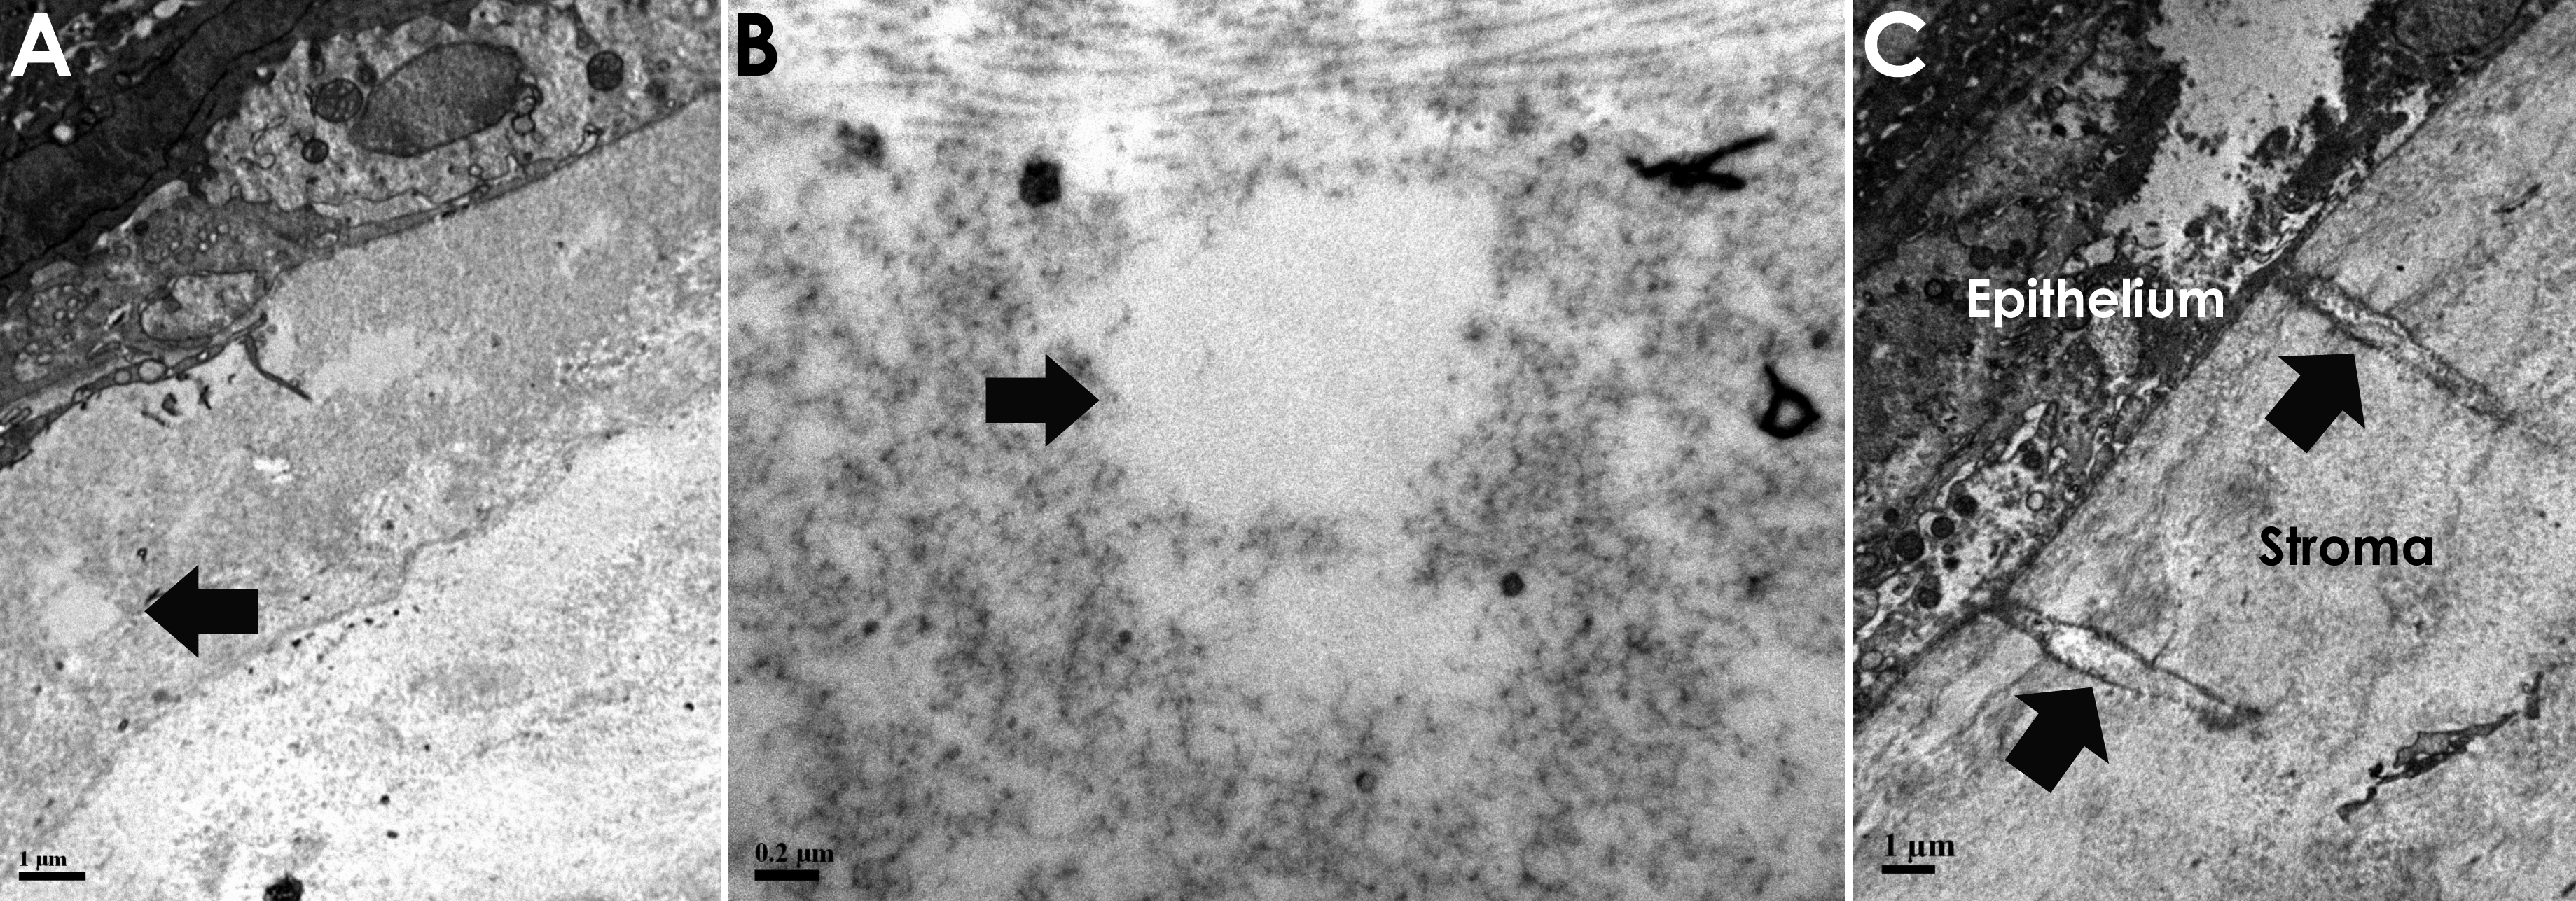

Figure 2. Transmission electron

micrographs (TEM) of the stroma within the area of the

femtosecond laser keratotomy. An individual cavitation is

highlighted (A, arrow). In the same image, epithelium is

seen superiorly (dark area containing cell contents). B:

An individual cavitation in greater detail. C: Streaks

consistent with laser pulses within the stroma, note that the

separation between streaks is roughly 5 microns.